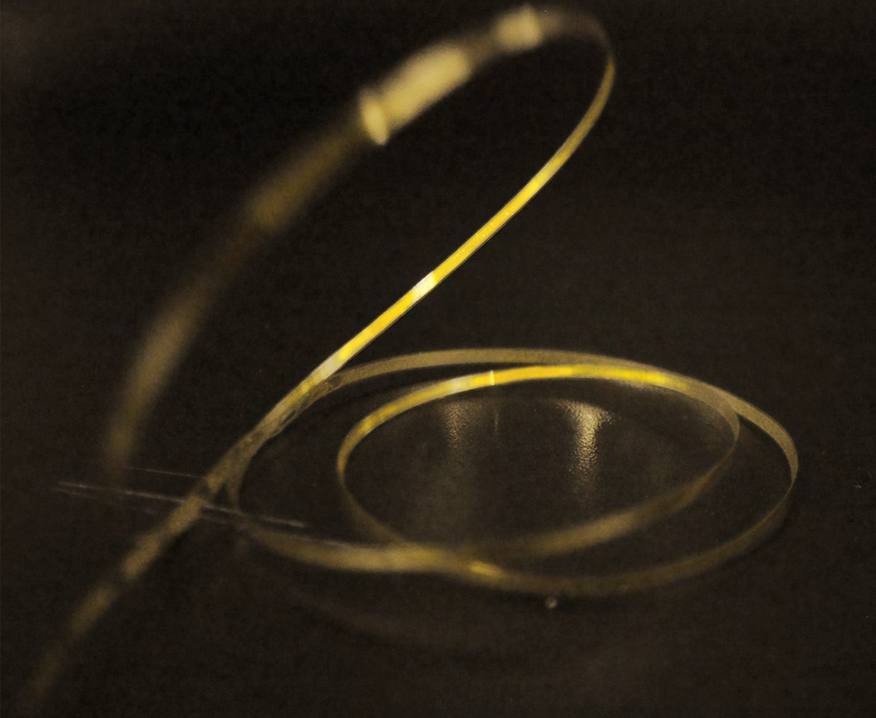

一次性使用球囊型冷冻消融导管

项目类型

器械质押区

起投金额

1200USDT

每日释放:0.75

释放周期:15 天

已购: 51666

剩余: 0